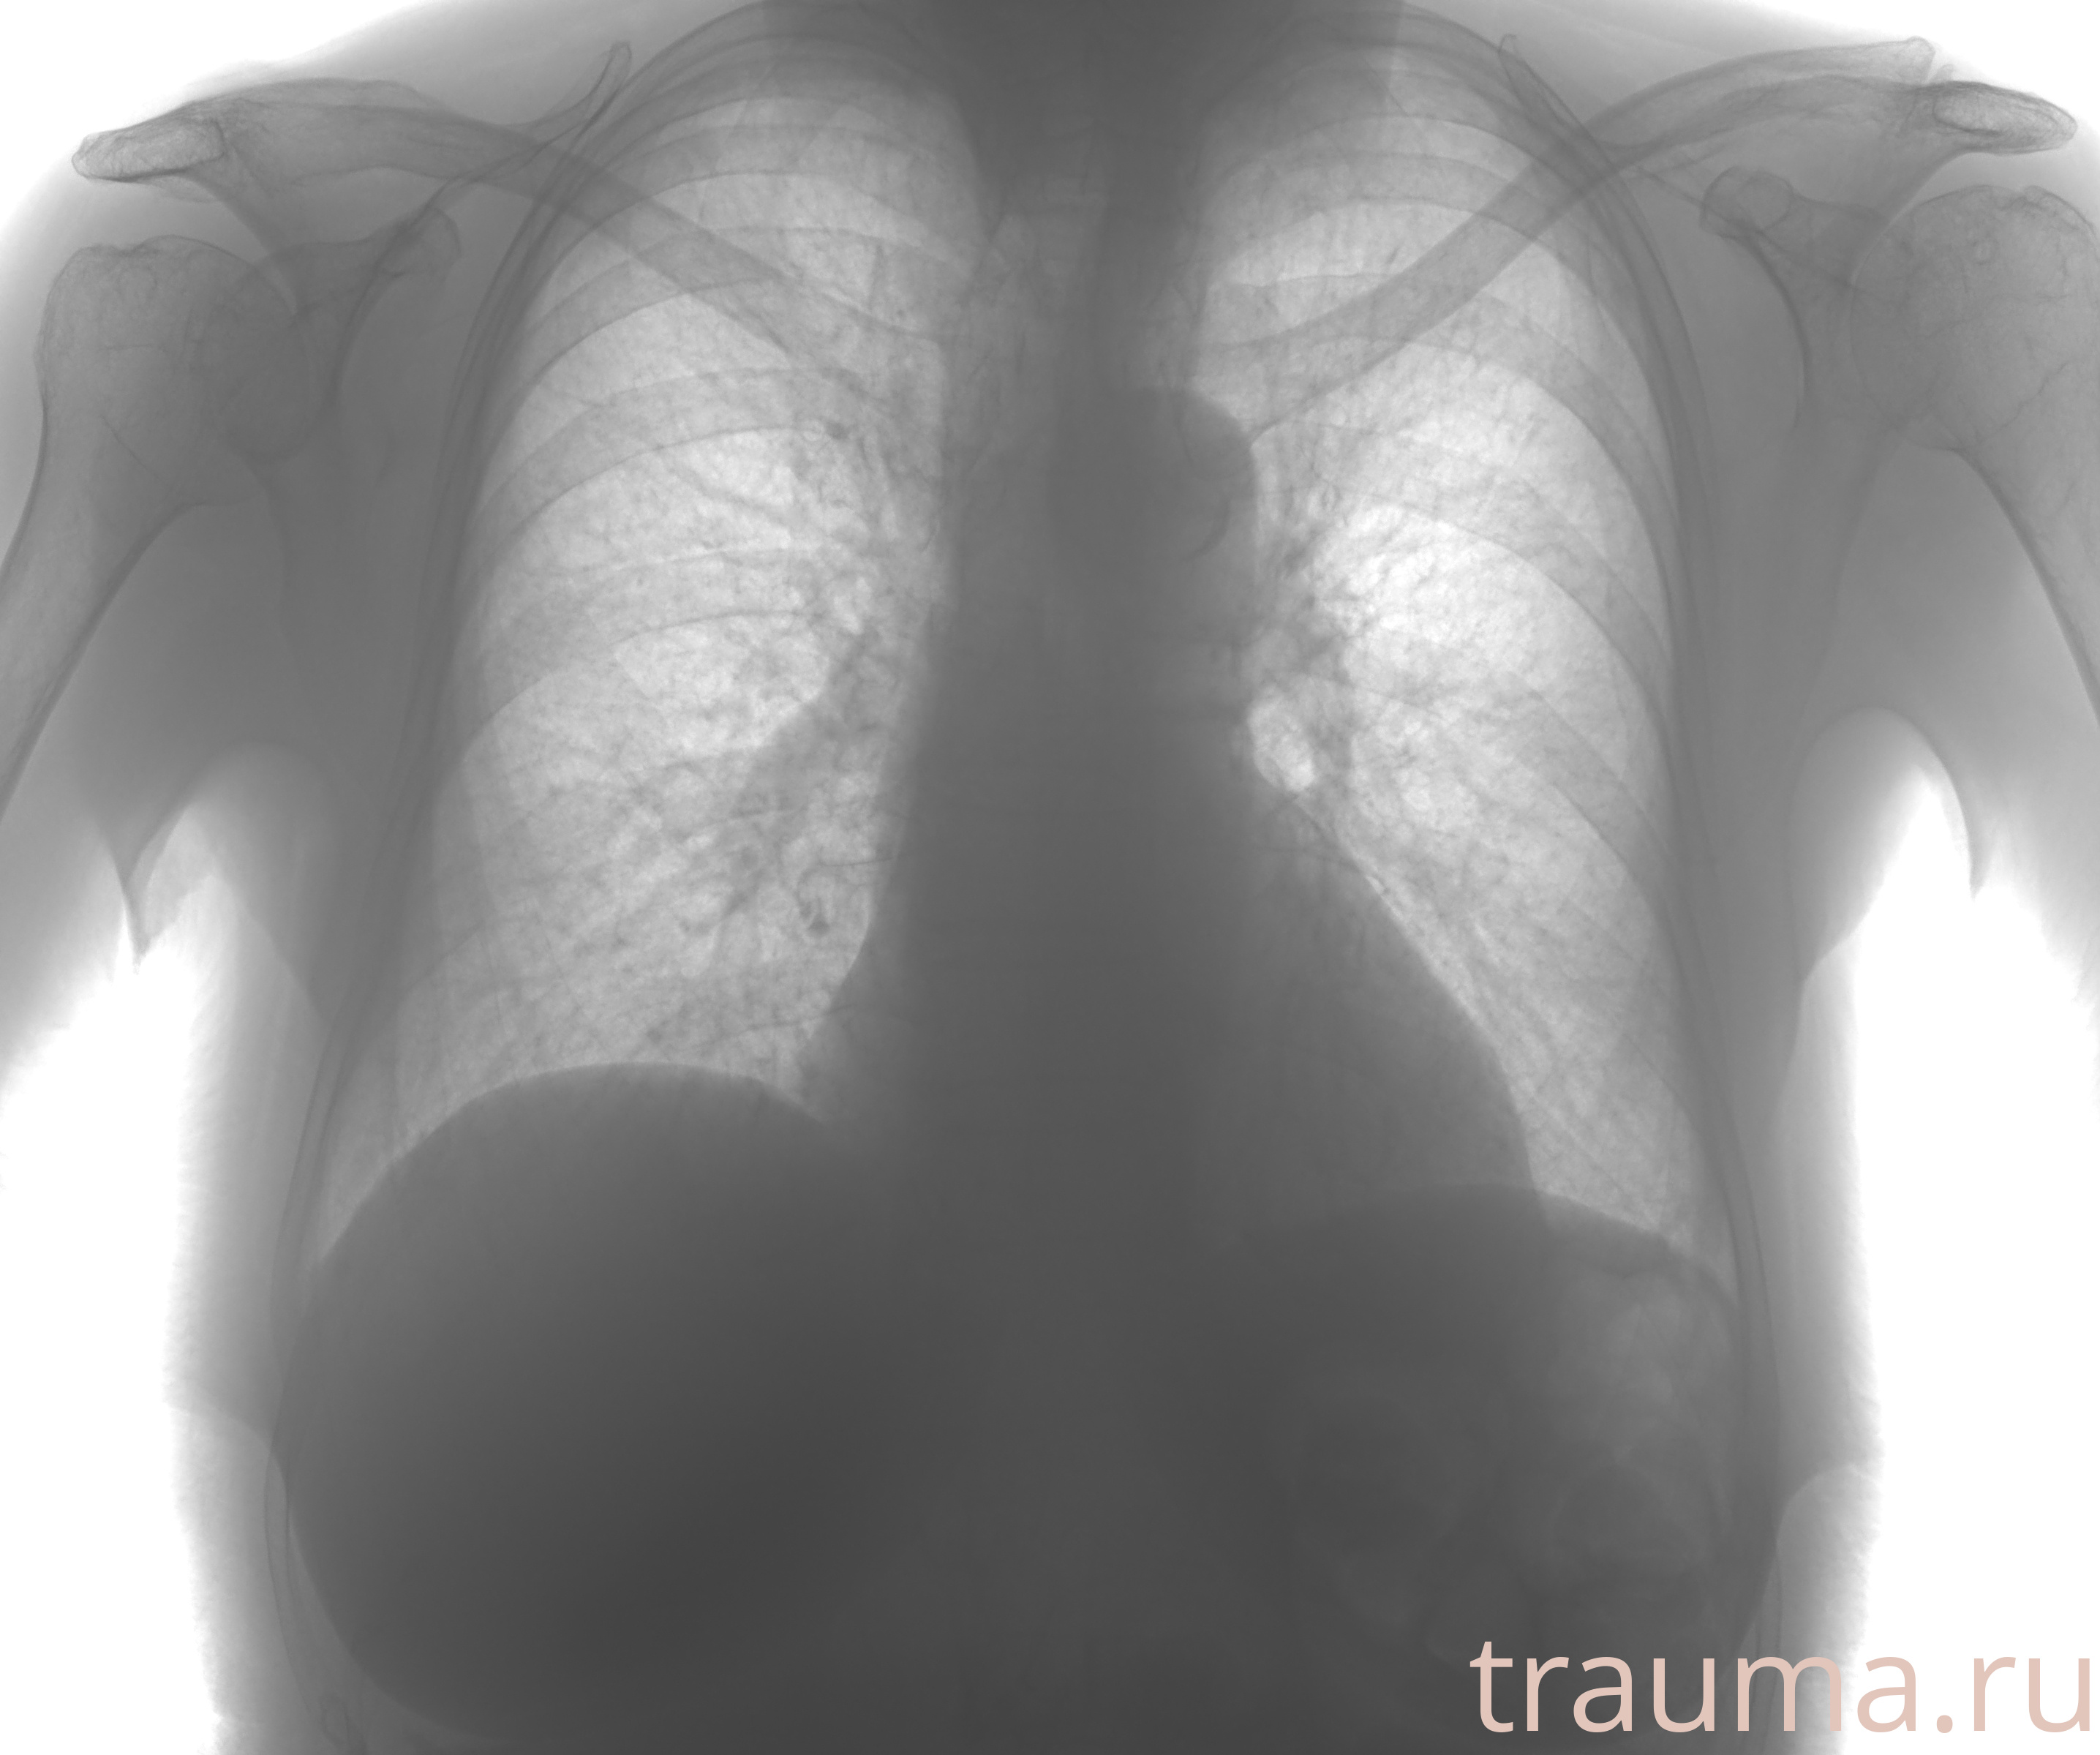

Рентгенограммы

Рентген на дому: по вашему адресу приезжает врач-рентгенолог, травматолог-ортопед с мобильным рентгеновским аппаратом, проводит диагностику травмы или заболевания, делает необходимые рентгенограммы, дает рекомендации по дальнейшему лечению. Получить качественные снимки в домашних условиях возможно благодаря уникальной методике, разработанной МосРентген Центром для института  Склифосовского